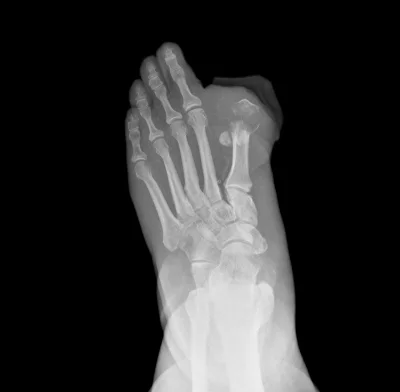

Diabetic foot occurs in 10% of all diabetics. It causes blockages and hardening of small to medium sized blood vessels particularly the vessels below the knee. Diabetic patients with peripheral vascular disease have an increased risk of heart attack, stroke and amputation.